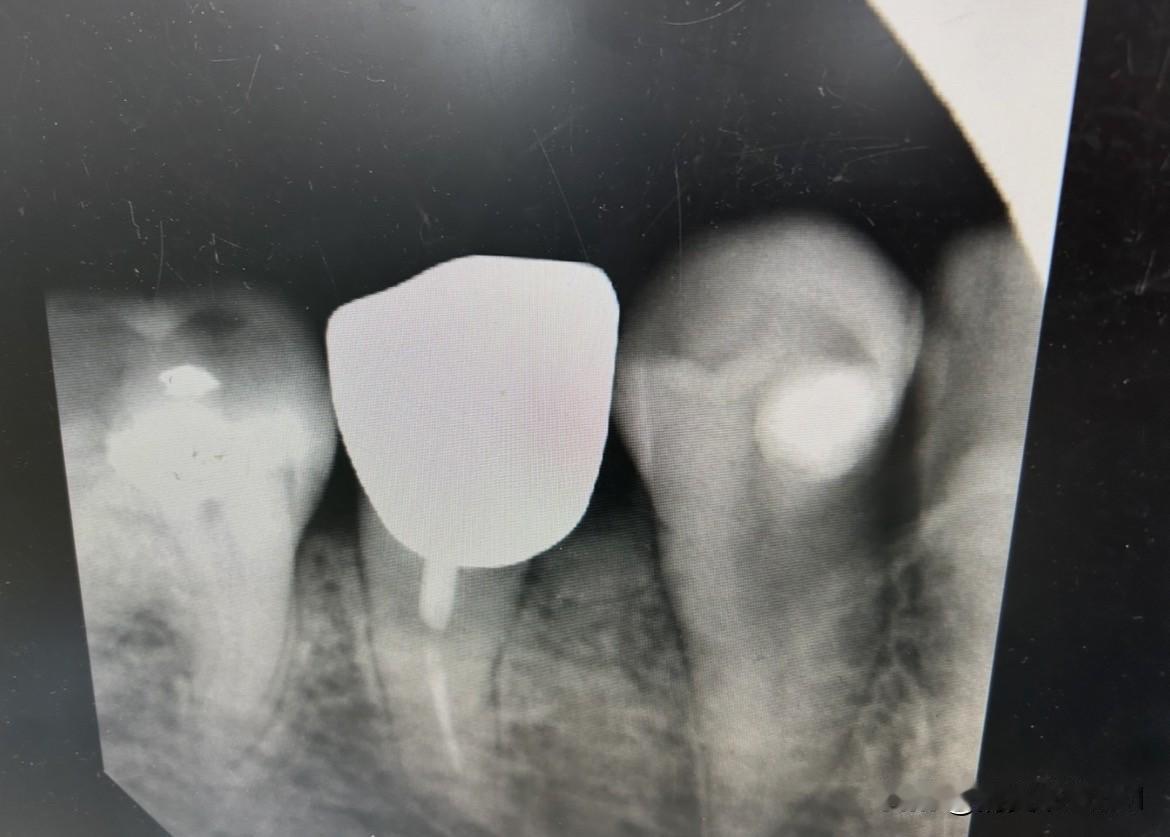

有个女的牙疼得受不了,实在扛不住就自己拔了牙。结果发现牙根上黏着一根白色线,也不知道是啥东西。网上有人说可能是以前做根管治疗留下的,也有人说可能是牙齿本身的矿物质纹路。 这事其实挺危险的,自己拔牙容易引发感染。现在好多人生病第一反应不是去医院,反而信小广告偏方。前几天新闻还说有人用钳子拔牙差点送命,最后住院花了一万多。 牙医解释说白色线可能是填充材料或者牙神经残留。建议大家别随便动别人牙齿,疼就赶紧去医院。这事到现在网上还在吵,估计以后还会爆出更多类似情况。